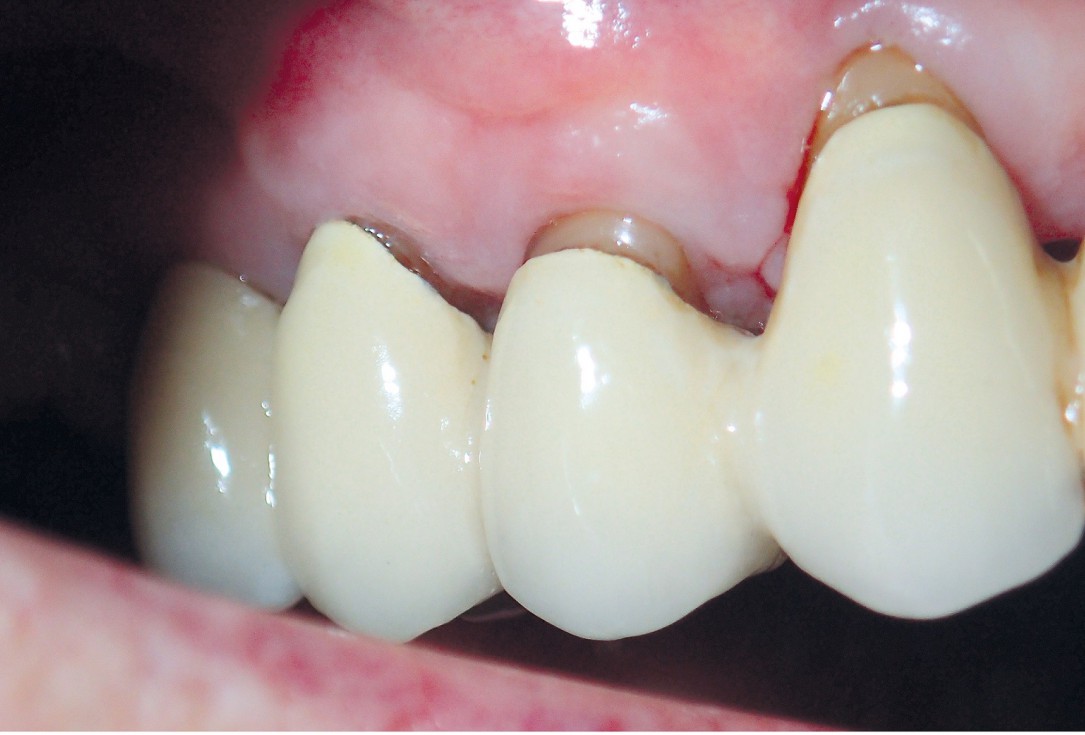

08/10 - Situation at the time of suture removal.GTR for the treatment of a deep three-dimensional intrabony defect using cerabone®, collprotect® membrane and Straumann® Emdogain® - Dr. T. Schwaar